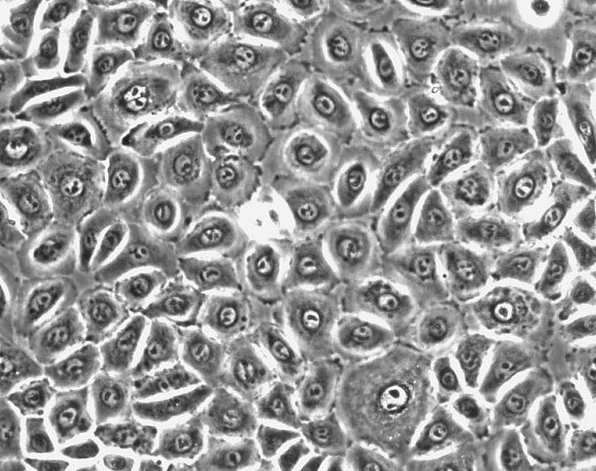

- 细胞形态:

上皮细胞样

形态:上皮细胞样

背景资料:该细胞由Gazdar AF及其同事于1979年从一名小细胞肺癌患者的骨髓转移灶中分离建立,该骨髓标本的获取先于患者的治疗。该细胞是一种典型的小细胞性肺癌细胞,表达较高水平的4种生化标志:神经特异性烯醇、肌酸激酶脑型同工酶、左旋多巴脱羧酶、铃蟾肽样免疫活性。c-myc DNA序列没有扩增;未发现大的结构DNA的异常;该细胞合成与正常肺相当量的p53 mRNA。该细胞以聚集体的形式悬浮生长,只有聚集体中的细胞是有活力的,但是细胞活率无法估计,一般培养基中含有大量的细胞碎片。